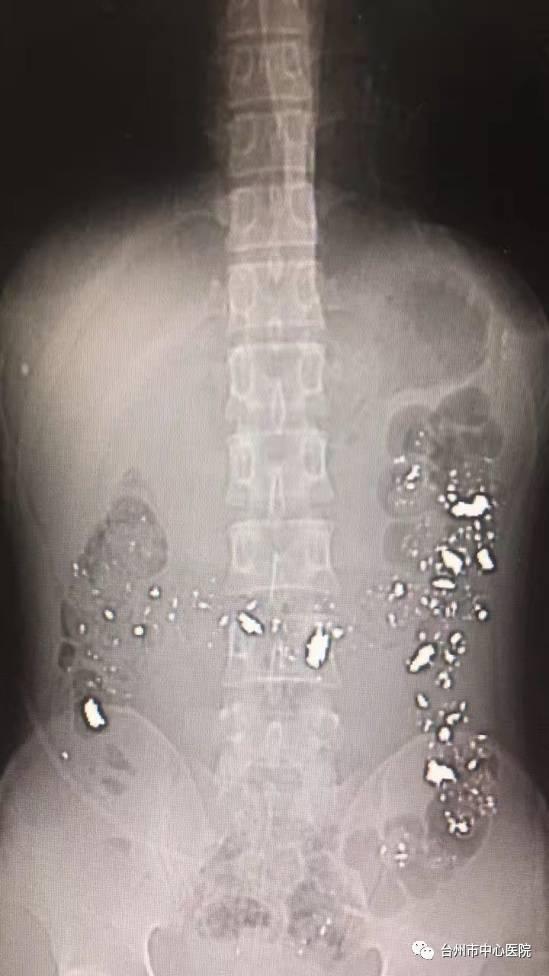

检查结果一出来,所有人都惊呆了!!!

他一肚子都是亮闪闪的金属!!!

以下腹部CT片

黄桔秀拿着CT片来到小伙子床边,小伙子这才说出实情——他食铅已经一年了!

“铅会对血液系统造成严重损害,难怪他贫血这么严重!“黄桔秀说,这下之前的疑问都得到了解答。